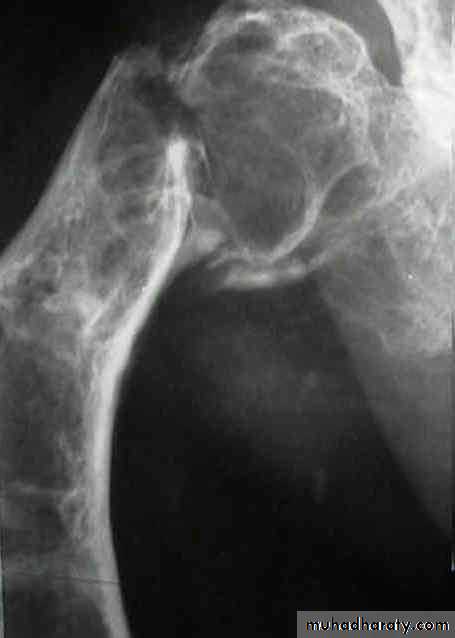

Fibrous dysplasia:

Developmental disorder whereby normal bone is replaced by fibrous tissue with flecks of osteoid.

It may affect one bone (monostotic) or multiple bones (polystotic).

The lesion may be very large causes bone expansion and cortical thinning with progressive deformity and sometimes pathological fracture.

Lesions occur in metaphysis&diaphysis, proximal femur is a common site it gives characteristic deformity called (shepherd’s-crock deformity(عصا الراعي.

X-ray shows lucent cystic lesion sometimes large and multilocular with bone expansion and cortical thinning it contains multiple calcific spots giving the ground-glass appearance, there is always possible deformity or pathological fracture.

About 5-10% of polyostotic forms get malignant, while only rarely occurs in monostotic lesions.

Treatment depends on tumor size and possible deformity;

Small lesions may need no treatment, just follow up.

For larger lesions we do curettage and bone graft or cement.

Sometimes we need internal fixation especially with fractures and larger lesions.

Deformities may need corrective osteotomy.

Always there is tendency for recurrence.